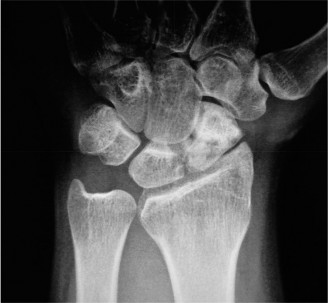

Identify neurovascular complications of perilunate injury? CASE 4 ### A patient presents with deep-seated pain in the mid-dorsal aspect of the wrist. There is no history of trauma. Examination is inconclusive except for some tenderness over the dorsal aspect of the scapholunate joint. X-ray (Fig. 3–6) is as follows. What is your diagnosis?

Figure 3–6(©) Sunil Thirkannad and Christine M. Kleinert.

The correct answer is (E). The x-ray shows a sclerotic lunate which should raise the suspicion of Kienbock’s disease.

The correct answer is (D). An ulna-negative variance, wherein the distal end of the ulna is shorter than the distal end of the sigmoid notch of the radius, is known to be associated with Kienbock’s disease. While the exact cause–effect relation between the two has not been established with certainty, it is hypothesized that a shorter ulna leads to increased loading at the radiolunate joint, predisposing the lunate to avascular necrosis.